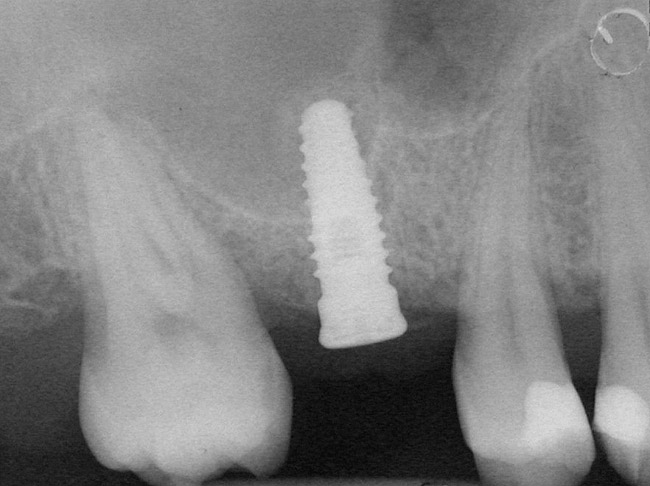

A 53-year-old female was referred for evaluation of a fracture of tooth No. 24. The tooth had been treated endodontically 5 years prior. The radiograph revealed a complete fracture of the tooth involving the crown (Figure 12). Tooth extraction and immediate placement of a an implant that was 10 mm in length and 3.75 in diameter was planned.

At the time of surgery, the tooth was extracted without harvesting any mucosal flap because the implant site was prepared by means of a pilot drill bur (Figure 13) and alternating osteotomes (Figure 14A and Figure 14B). The implant was positioned and showed primary stability. The implant was loaded 2 days after surgery. Then, splinted PFM crowns supported by custom gold abutments were delivered. At 6 months posttreatment, the radiograph revealed no bone resorption and the clinical result was optimal (Figure 15A and Figure 15B).

Figure 12  Preoperative radiograph shows fractured tooth No. 24.

Figure 12

Figure 15  Posttreatment radiograph, 6 months after the initial surgery.

Figure 15b